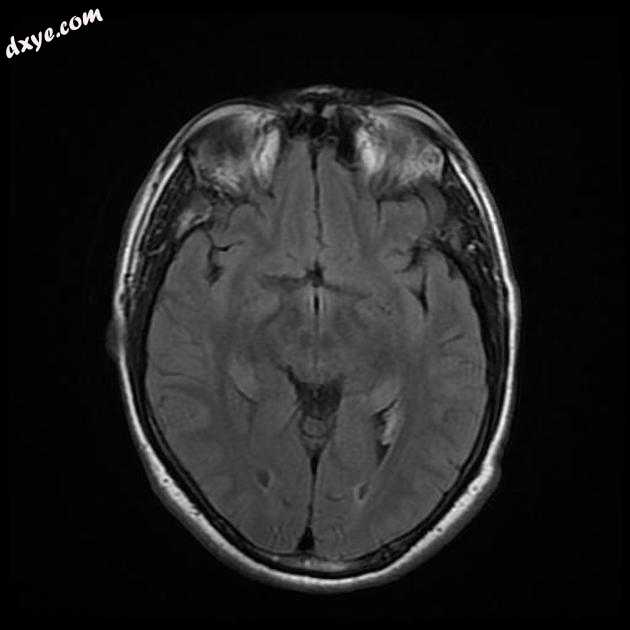

Axial FLAIR

3.jpeg

MRI 序列显示右侧颈内动脉的部分血栓囊状动脉瘤位于 C6/7 节段的交界处,大小为 11 x 7 毫米,颈部为 2.5 毫米,压迫动眼神经 (III) 的相邻节段,在 T1 上清晰可见和 FIESTA 序列。

位于 C6/7 交界处的右侧颈内动脉部分血栓囊状动脉瘤的 MRI 特征,压迫同侧动眼神经 (III)。